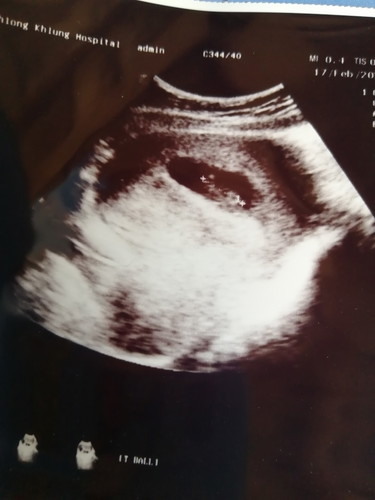

สอบถามหน่อยค่ะ อายุครรภ์ได้13+5แต่เด็กตัวเล็กมาก มองแทบไม่เห็น เลยอยากรู้ว่าอายุครรภ์ประมาณนี้ขนาดของน้องควรอยู่ประมาณไหนค่ะมีแม่ๆบ้านไหนขนาดของน้องตัวน้อยแบบนี้บ้างค่ะกังวลมากค่ะกลัวลูกจะไม่โต

ของแม่บ้านนี้ค่ะ ตอนนี้13wแล้ว